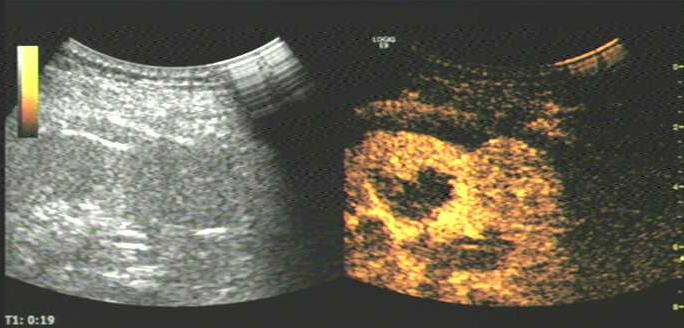

图片6.png

造影剂注射后19S;肾皮质第随后自髓质外部逐渐向内部增强;

可见上述肾脏占位稍晚于肾实质增强,病灶呈整体均匀增强;